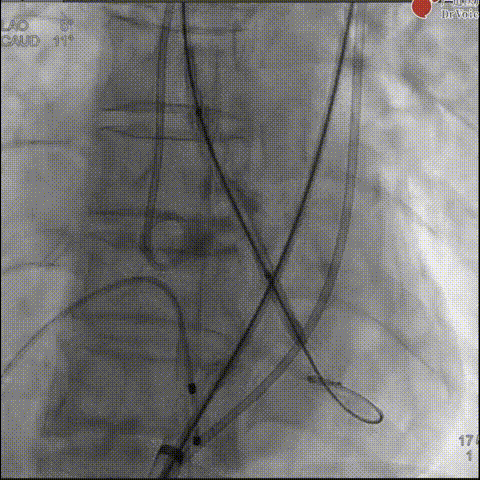

首例患者为典型的Type 0型二叶式主动脉瓣重度狭窄,手术团队结合术前超声,经充分讨论综合评估后,计划植入23mm人工瓣膜,约8-10% oversize。

术中,团队顺利完成瓣膜输送、定位与释放,术后评估显示瓣膜位置满意,功能良好,未见明显瓣周漏,为后续高难度病例的演示奠定良好开端。

瓣膜释放